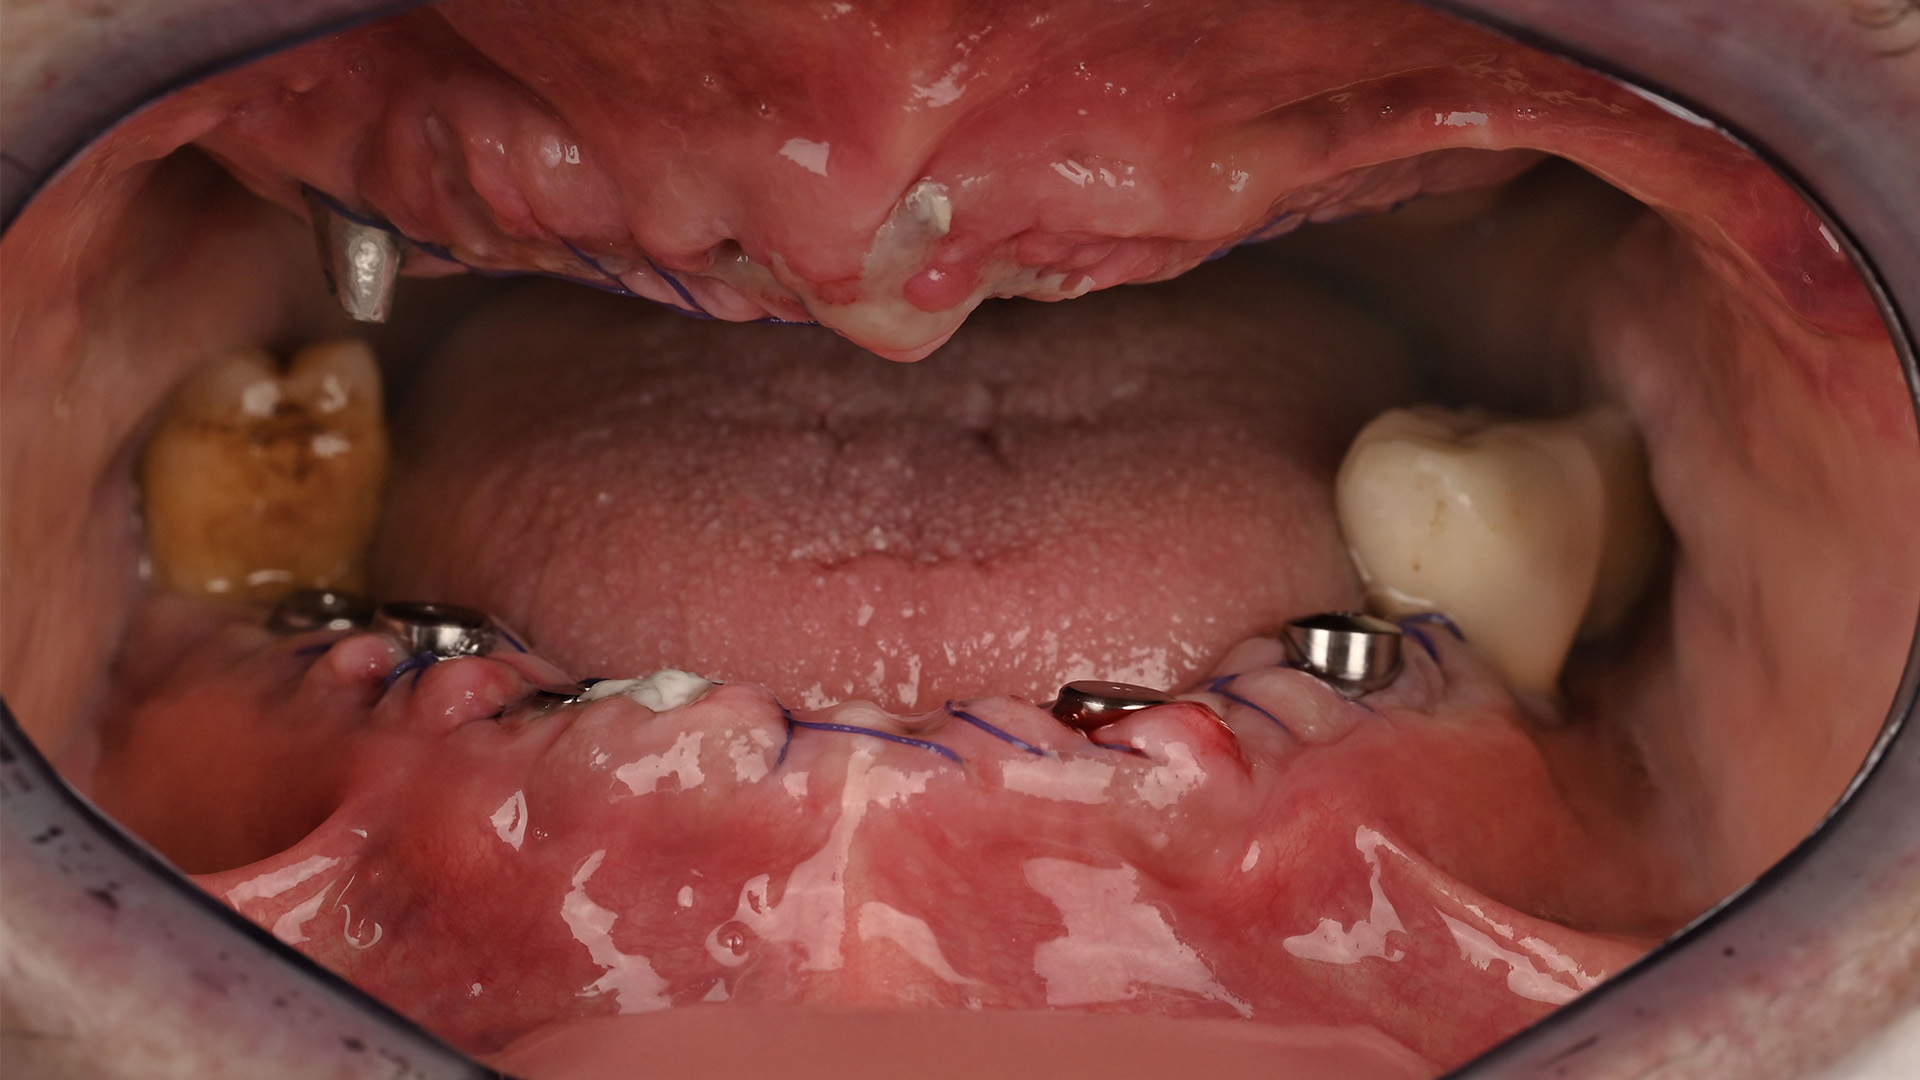

Hastalarımıza uyguladığımız tedaviler arasında diş dolgusu, kanal tedavisi, diş çekimi, diş beyazlatma, diş implantı, diş teli (ortodontik tedavi), porselen veya zirkonyum kaplama, laminate veneer, diş taşı temizliği ve polisaj, periodontal tedavi, protez uygulamaları ve gülüş tasarımı gibi çeşitli hizmetler bulunmaktadır. Bu tedaviler, hastalarımızın ağız sağlığını korumak ve estetik ihtiyaçlarını karşılamak amacıyla kişiye özel planlanmakta ve en iyi sonuçlar için titizlikle uygulanmaktadır.

Hastalarımıza uyguladığımız tedaviler arasında diş dolgusu, kanal tedavisi, diş çekimi, diş beyazlatma, diş implantı, diş teli (ortodontik tedavi), porselen veya zirkonyum kaplama, laminate veneer, diş taşı temizliği ve polisaj, periodontal tedavi, protez uygulamaları ve gülüş tasarımı gibi çeşitli hizmetler bulunmaktadır. Bu tedaviler, hastalarımızın ağız sağlığını korumak ve estetik ihtiyaçlarını karşılamak amacıyla kişiye özel planlanmakta ve en iyi sonuçlar için titizlikle uygulanmaktadır.

Hastalarımıza uyguladığımız tedaviler arasında diş dolgusu, kanal tedavisi, diş çekimi, diş beyazlatma, diş implantı, diş teli (ortodontik tedavi), porselen veya zirkonyum kaplama, laminate veneer, diş taşı temizliği ve polisaj, periodontal tedavi, protez uygulamaları ve gülüş tasarımı gibi çeşitli hizmetler bulunmaktadır. Bu tedaviler, hastalarımızın ağız sağlığını korumak ve estetik ihtiyaçlarını karşılamak amacıyla kişiye özel planlanmakta ve en iyi sonuçlar için titizlikle uygulanmaktadır.

Hastalarımıza uyguladığımız tedaviler arasında diş dolgusu, kanal tedavisi, diş çekimi, diş beyazlatma, diş implantı, diş teli (ortodontik tedavi), porselen veya zirkonyum kaplama, laminate veneer, diş taşı temizliği ve polisaj, periodontal tedavi, protez uygulamaları ve gülüş tasarımı gibi çeşitli hizmetler bulunmaktadır. Bu tedaviler, hastalarımızın ağız sağlığını korumak ve estetik ihtiyaçlarını karşılamak amacıyla kişiye özel planlanmakta ve en iyi sonuçlar için titizlikle uygulanmaktadır.

Hastalarımıza uyguladığımız tedaviler arasında diş dolgusu, kanal tedavisi, diş çekimi, diş beyazlatma, diş implantı, diş teli (ortodontik tedavi), porselen veya zirkonyum kaplama, laminate veneer, diş taşı temizliği ve polisaj, periodontal tedavi, protez uygulamaları ve gülüş tasarımı gibi çeşitli hizmetler bulunmaktadır. Bu tedaviler, hastalarımızın ağız sağlığını korumak ve estetik ihtiyaçlarını karşılamak amacıyla kişiye özel planlanmakta ve en iyi sonuçlar için titizlikle uygulanmaktadır.

Hastalarımıza uyguladığımız tedaviler arasında diş dolgusu, kanal tedavisi, diş çekimi, diş beyazlatma, diş implantı, diş teli (ortodontik tedavi), porselen veya zirkonyum kaplama, laminate veneer, diş taşı temizliği ve polisaj, periodontal tedavi, protez uygulamaları ve gülüş tasarımı gibi çeşitli hizmetler bulunmaktadır. Bu tedaviler, hastalarımızın ağız sağlığını korumak ve estetik ihtiyaçlarını karşılamak amacıyla kişiye özel planlanmakta ve en iyi sonuçlar için titizlikle uygulanmaktadır.

Hastalarımıza uyguladığımız tedaviler arasında diş dolgusu, kanal tedavisi, diş çekimi, diş beyazlatma, diş implantı, diş teli (ortodontik tedavi), porselen veya zirkonyum kaplama, laminate veneer, diş taşı temizliği ve polisaj, periodontal tedavi, protez uygulamaları ve gülüş tasarımı gibi çeşitli hizmetler bulunmaktadır. Bu tedaviler, hastalarımızın ağız sağlığını korumak ve estetik ihtiyaçlarını karşılamak amacıyla kişiye özel planlanmakta ve en iyi sonuçlar için titizlikle uygulanmaktadır.

Hastalarımıza uyguladığımız tedaviler arasında diş dolgusu, kanal tedavisi, diş çekimi, diş beyazlatma, diş implantı, diş teli (ortodontik tedavi), porselen veya zirkonyum kaplama, laminate veneer, diş taşı temizliği ve polisaj, periodontal tedavi, protez uygulamaları ve gülüş tasarımı gibi çeşitli hizmetler bulunmaktadır. Bu tedaviler, hastalarımızın ağız sağlığını korumak ve estetik ihtiyaçlarını karşılamak amacıyla kişiye özel planlanmakta ve en iyi sonuçlar için titizlikle uygulanmaktadır.

Hastalarımıza uyguladığımız tedaviler arasında diş dolgusu, kanal tedavisi, diş çekimi, diş beyazlatma, diş implantı, diş teli (ortodontik tedavi), porselen veya zirkonyum kaplama, laminate veneer, diş taşı temizliği ve polisaj, periodontal tedavi, protez uygulamaları ve gülüş tasarımı gibi çeşitli hizmetler bulunmaktadır. Bu tedaviler, hastalarımızın ağız sağlığını korumak ve estetik ihtiyaçlarını karşılamak amacıyla kişiye özel planlanmakta ve en iyi sonuçlar için titizlikle uygulanmaktadır.

Hastalarımıza uyguladığımız tedaviler arasında diş dolgusu, kanal tedavisi, diş çekimi, diş beyazlatma, diş implantı, diş teli (ortodontik tedavi), porselen veya zirkonyum kaplama, laminate veneer, diş taşı temizliği ve polisaj, periodontal tedavi, protez uygulamaları ve gülüş tasarımı gibi çeşitli hizmetler bulunmaktadır. Bu tedaviler, hastalarımızın ağız sağlığını korumak ve estetik ihtiyaçlarını karşılamak amacıyla kişiye özel planlanmakta ve en iyi sonuçlar için titizlikle uygulanmaktadır.